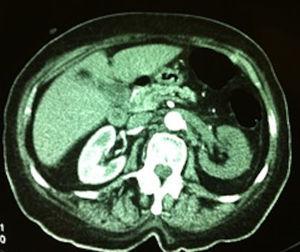

Un renograma dietiltriaminopentaacético (DTPA) confirmó ausencia de flujo sanguíneo en la arteria renal izquierda, y la angio-TAC (tomografía axial computarizada) con contraste mostró un trombo en el origen de la arteria renal izquierda con oclusión total de esta (figura 2).

Figura 2. Angio-tomografía axial computarizada: muestra ausencia de contraste en el riñón izquierdo con oclusión al inicio de la arteria ipsilateral.